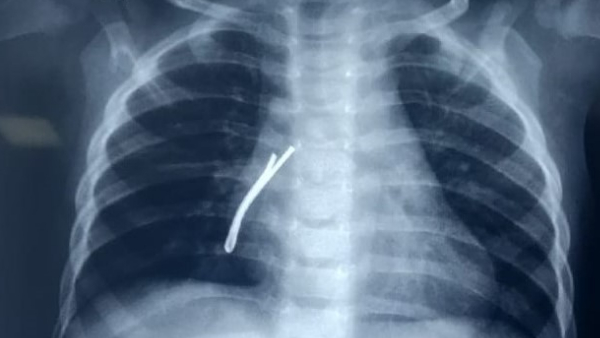

एम्स के डॉ विकास गुप्ता ने जानकारी देते हुए बताया कि हमने बच्चे की जांच के लिए ईएनटी सर्जनों की टीम बनाई। इसके बाद गहन जांच की गई। उसकी छाती की इमरजेंसी रेडियोग्राफी कराई गई। वही हाई रेगुलेशंस सीटी (कंप्यूटेड टोमोग्राफी) की गई। जिसकी रिपोर्ट सामने आने के बाद बच्चे के दाहिने फेफड़े यानी राइट ब्रोंकस की श्वास नली के निचले हिस्से में एक लंबा हेयर पिन फंसा दिखाई दिया।

4 सेंटीमीटर हेयर पिन को निकाला बाहर

इसके बाद टीम ने बच्ची को ऑपरेशन थिएटर के लिए रेडी किया गया। बच्ची को पहले सामान्य एनेस्थिसिया दी गई। इसकी मदद से बच्ची की आपातकालीन रिजिड ब्रोंकोस्कोपी की गई। बच्चे की दाहिनी तरफ श्वसन नली यानी ब्रोंकस से ऑप्टिकल चिमटे का उपयोग करते हुए हैरपीन को निकाला गया। यह हैरपीन करीब 4 सेंटीमीटर लंबी थी डॉक्टरों के मुताबिक श्वास नली में इस तरह की कोई भी भारी वस्तु फंस जाए तो वह जानलेवा हो सकती है।